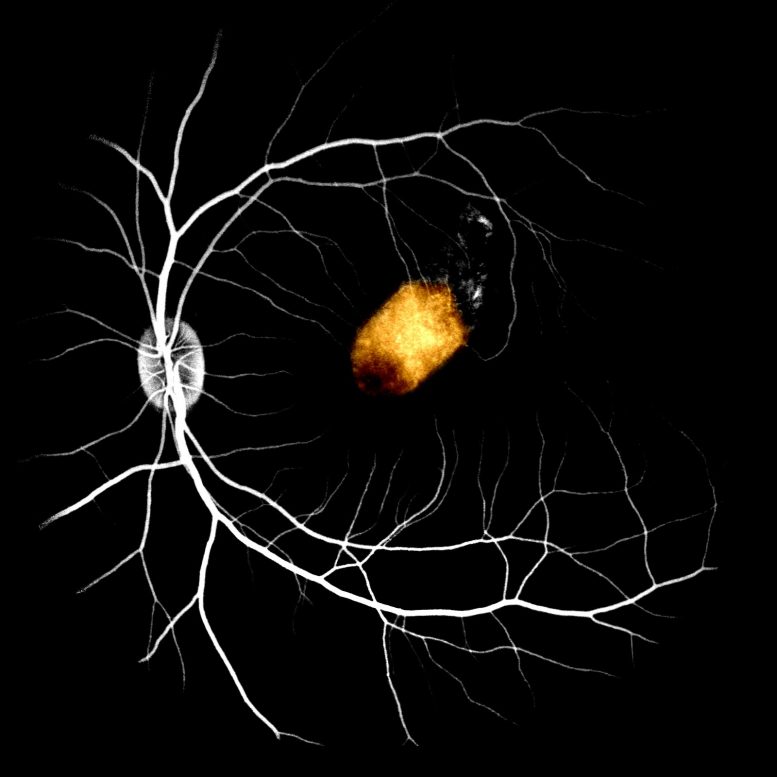

这是嵌入在非人类灵长类动物模型的次视网膜空间中的RPE植入物的图像。眼镜荧光素血管造影突出的背景视网膜血管。

根据刘,等最近公布的脉动细胞报告的研究,源自成人人眼干细胞的源自成人人眼干细胞的视网膜细胞在移植到猴子的眼睛中存活。视网膜颜料上皮(RPE),视网膜中的一层着色细胞,对于维持正常视觉至关重要。由于RPE功能障碍(例如黄斑变性)的失明影响全世界约2亿人。

该研究是第一次评估非人印象中成人视网膜干细胞衍生RPE移植的安全性和可行性。研究人员发现,RPE贴片移植到猴眼的眼睛中,稳定地整合至少三个月,没有严重的副作用。更重要的是,干细胞衍生的RPE部分接管猴RPE的功能,并且能够支持正常的感光功能。重要的是,这些细胞没有导致视网膜瘢痕形成。